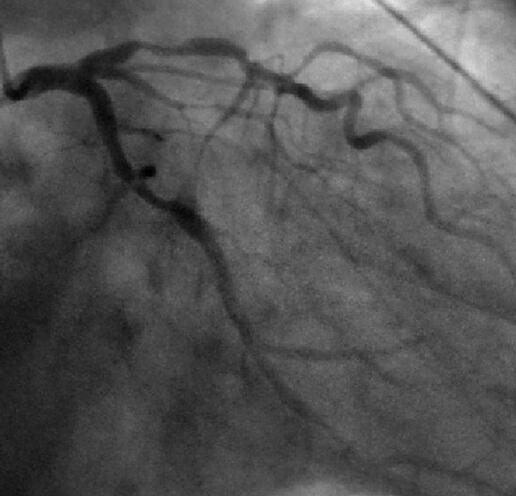

2010年5月冠脉造影示:冠脉三支病变(累及LAD、LCX、RCA),其中前降支近段85%~90%节段性狭窄,旋支近中段99%节段性狭窄,右冠状动脉近中段90%节段性狭窄。分别干预前降支及旋支,植入支架(图2-11-1)。

图2-11-1 2010年5月冠脉造影及PCI术